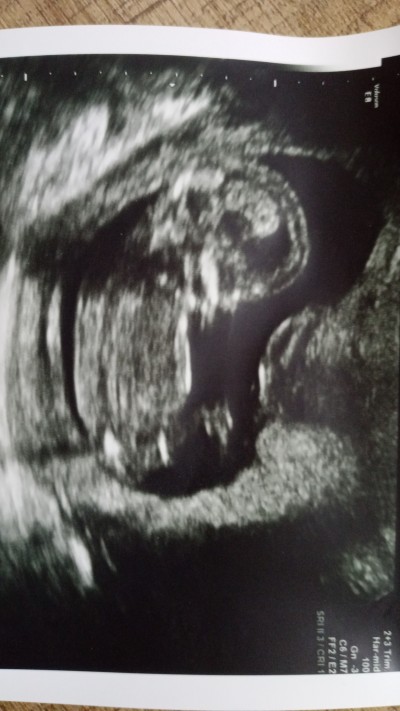

Sizce cinsiyeti nedir 14+3 oldu hala doktor söylemedi

image